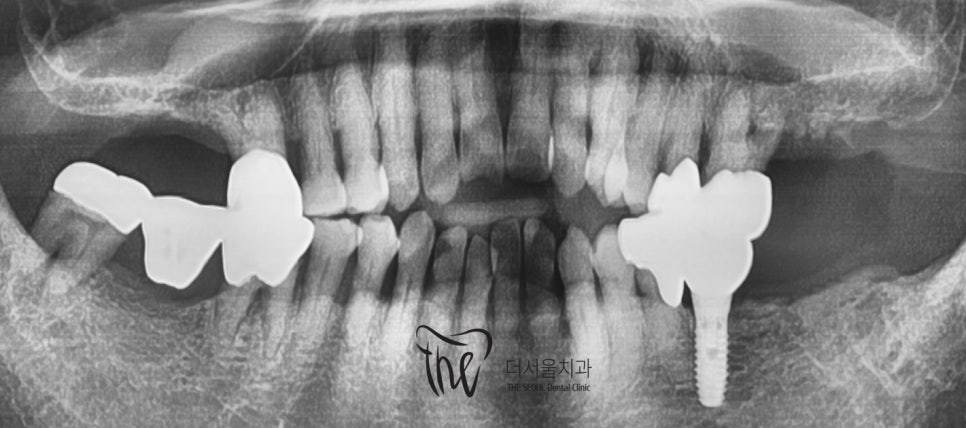

그리고, 오랜 시간 치주염을 앓아오셨기 때문에

잇몸 퇴축 뿐만이 아니라 치조골의 위축 또한

상당히 진행 된 채로 오셨었죠.

이미 임플란트 시술 또는 크라운 보철이

다 수복이 되어 있습니다.

이 분은, 대략 1년 가량 치료기간을 잡고

진행을 하기로 하셨습니다.

이미 나이가 어느정도 있는지라,.

굳이 개방교합 교정 은 받기 싫다 하셨으며

잇몸치료 및 치아 결손 부위의 임플란트 대체로만

진료를 받기로 하셨었습니다.

치료 기간 2020.03.01 ~ 2021.05.01